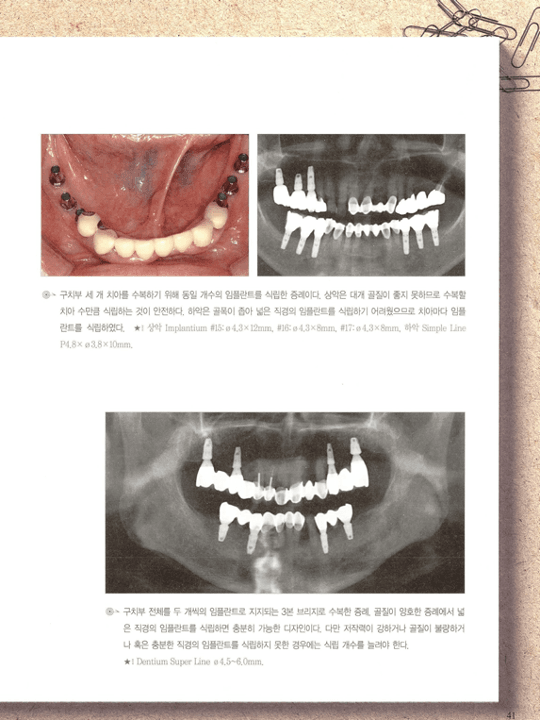

[그림 3] 구치부 임플란트 식립 임상 증례. 잔존 치조골과 인접치 간 거리를 고려해 규격과 개수를 결정한 실제 식립 결과를 파노라마에서 확인합니다.

공간 < 12mm

두 개 임플란트를 배치하면 간격이 부족해지거나 치근 간 거리가 좁아져 장기적으로 변연골 흡수와 유지관리 문제가 생길 수 있습니다. 이 경우 단일 임플란트에 넓은 교합면 보철을 설계하는 편이 유리할 수 있습니다.

공간 ≥ 14mm

두 개 임플란트를 적절한 간격(최소 3mm)으로 배치해 교합력을 분산시키는 것이 기계적 안정성과 변연골 건강 면에서 유리합니다.